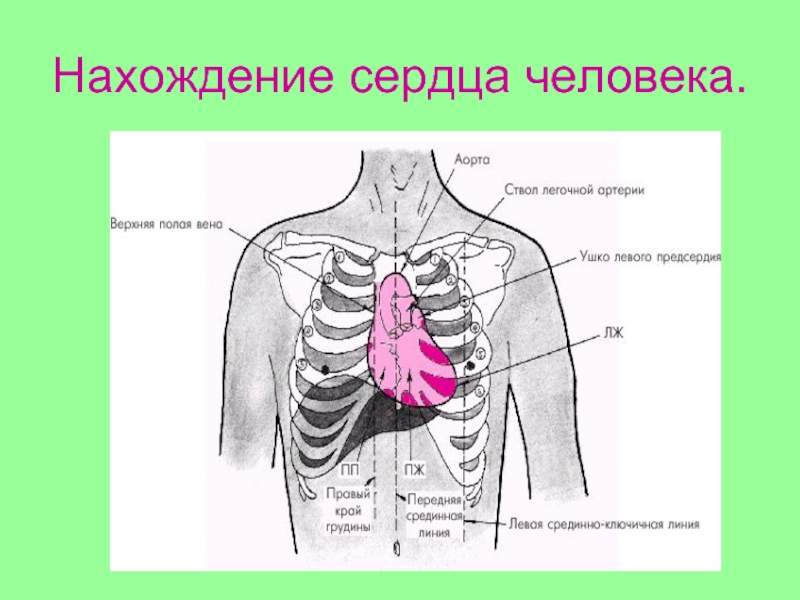

Где находится сердце у человека.

Сердце у человека располагается в грудной полости.

Расположение сердца у человека.

Анатомическое расположение сердца.

Сердце в грудной клетке расположено.

Где расположено сердце у человека анатомия.